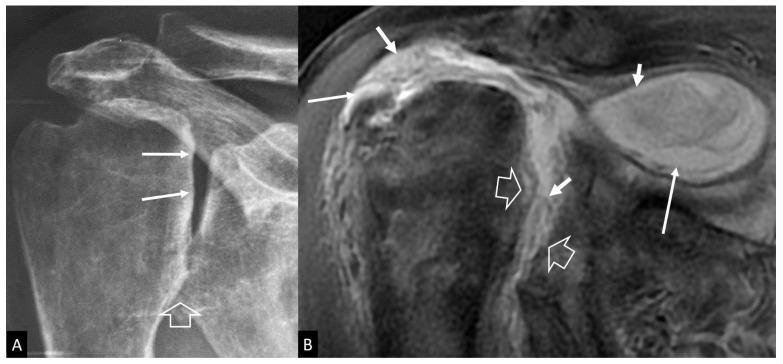

A series of conditions can mimic musculoskeletal infections on imaging, complicating their diagnosis and affecting the treatment. Depending on the anatomical location, different conditions can manifest with clinical and imaging findings that mimic infections. Herein we present a wide spectrum of the musculoskeletal disorders of the axial skeleton, long bones, peripheral joints, and soft tissue that may manifest as infectious processes, and we focus on the potential mimics of osteomyelitis, septic arthritis, and infectious spondylodiscitis that are common in clinical practice. We present the typical imaging characteristics of each musculoskeletal infection, followed by mimicking conditions.

一系列病症在影像学上可模拟肌肉骨骼感染,使诊断复杂化并影响治疗。根据解剖位置的不同,不同病症可表现出类似感染的临床和影像学表现。在此,我们展示了轴向骨骼、长骨、外周关节和软组织的广泛肌肉骨骼疾病,这些疾病可能表现为感染过程,并且我们重点关注临床实践中常见的骨髓炎、化脓性关节炎和感染性脊椎间盘炎的潜在模仿病症。我们介绍了每种肌肉骨骼感染的典型影像学特征,随后是模仿病症。